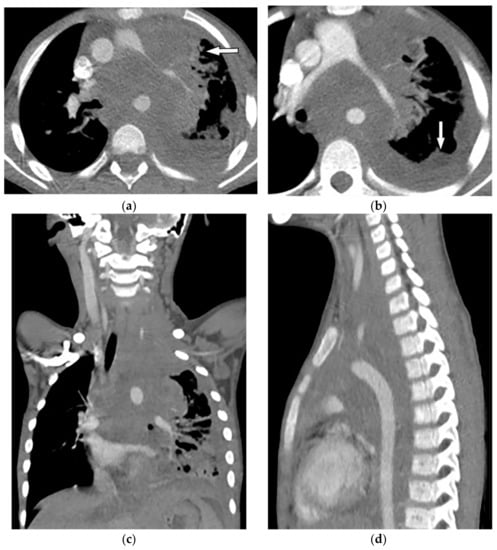

8.2. Tuberculosis Spondylodiskitis

Tuberculosis spondylodiskitis has a more gradual and chronic clinical course, which leads to multi-level involvement and paravertebral cold abscess formation with well-circumscribed thin wall. Subligamentous spread of infection to adjacent vertebral levels, relative preservation of intervertebral disk, and kyphotic angulation (gibbous deformity) are other imaging findings. CT scan is more sensitive in delineating calcification within paravertebral cold abscess, end plate erosion, and bony fragment visualization (Figure 13) [39,42].

Figure 13.

A 65-year-old man with fever, weight loss, and night sweeting. The non-contrast-enhanced CT (bone window) in axial plane (a) shows paraspinal soft tissue mass with erosion of right lateral aspect of adjacent vertebral body. Sagittal T2W image of another patient with the same pathology (b) shows hypersignal intensity within T8-T9 vertebral bodies with also intervertebral disc destruction and narrowing of spinal canal pushing the spinal cord posteriorly. Axial T1WFS + C (c) identified the enhancing paraspinal mass with peripheral rim enhancement (arrow) in its left posteromedial side, which is suggestive of abscess formation. Culture of aspirated pus under guide of CT was compatible with tuberculosis infection.